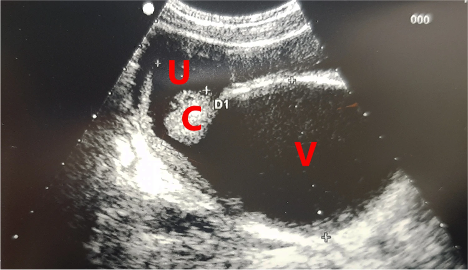

Figure 1: Transabdominal ultrasound findings of hematometrocolpos

V = vagina dilated by blood; C = cervix; U = uterus with initial distension of cavity

Taken from “Hematocolpos due to imperforate hymen: a case report and literature systematic review” [2]

Hematocolpos is an uncommon condition, most often due to an imperforate hymen, wherein menstrual blood fills the vagina and is trapped there. The blood typically accumulates over the course of several menstrual cycles, eventually causing distention of the vaginal canal, with associated symptoms.  Hematocolpos typically presents with a variety of symptoms, such as lower abdominal pain, urinary complaints, back pain, and/or constipation. Physical exam reveals a thin membrane overlying a blueish bulging mass at the introitus, which is pathognomonic for the condition. Ultrasound can also be helpful to aid in the diagnosis, which may show a distended, fluid-filled vaginal canal. If the uterus also contains accumulated menstrual blood, the patient may appear to have a large pelvic mass on ultrasound, or a distended, fluid filled uterus. If the uterus is involved, the condition is termed hematometrocolpos (see Figure 1).